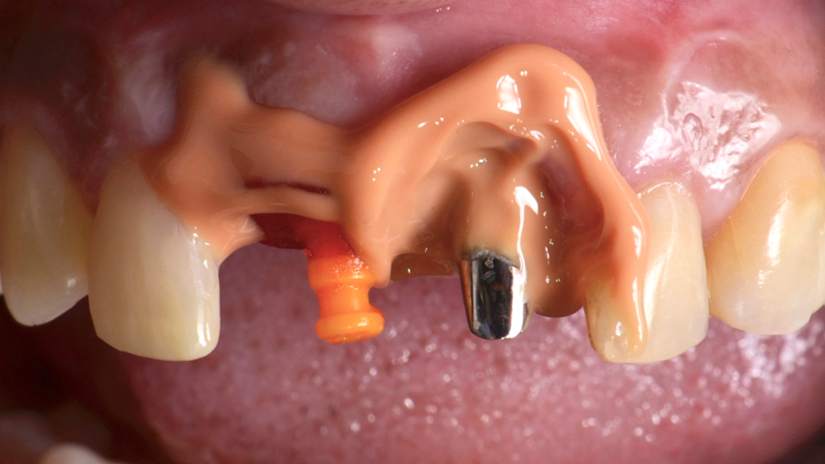

A paciente apresentava queixas estéticas e funcionais. Após avaliação clínica e radiográfica, optou-se pela substituição do pilar reto por um pilar Ideale angulado de 17 graus e 3,3 mm de diâmetro. Esse componente mais estreito e angulado permitiu corrigir o eixo emergente da futura coroa, viabilizando o planejamento de uma prótese parafusada na região estética.

O caso foi conduzido com planejamento cuidadoso, moldagens analógicas e provas clínicas. A reabilitação foi finalizada com a instalação de uma coroa metalocerâmica parafusada, garantindo estética, funcionalidade e reversibilidade do conjunto protético.